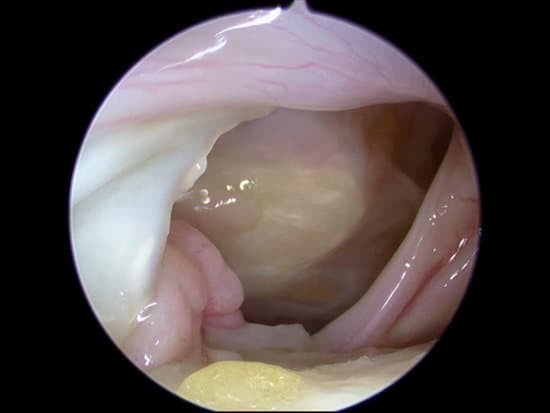

3. 수술 방법

회전근개를 봉합한 뒤, 그 위에 인공 보강재를 덮어 앵커로 고정

봉합 부위가 받는 장력을 분산시키고, 새 조직이 자라날 수 있는 기질(Scaffold) 역할을 함